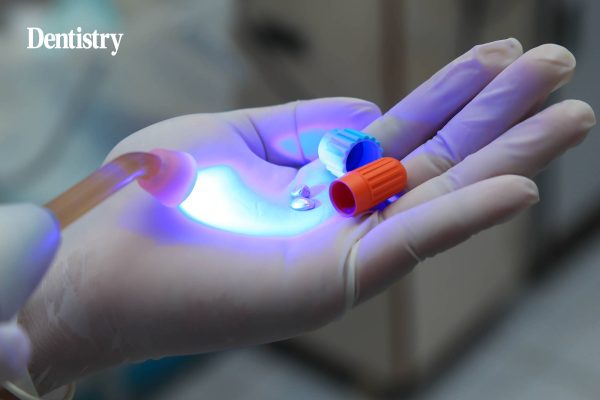

Amalgam alternatives – supporting everyday speed and efficiency

Amalgam has been used in dentistry since the 1800s, when it was first established as a strong, durable and versatile…

Amalgam alternatives – what is driving the change?

Kemdent explains what’s driving the move away from amalgam and what to look out for when choosing between the alternatives…

Amalgam alternatives

Kemdent explains the reasons why amalgam is no longer the preferred restorative dental material and offer a viable alternative. Amalgam…

Amalgam – can it still look as beautiful as its compatriot?

Rizwaan Chaudhary makes the case for amalgam restorations and explains why he thinks it is superior to composites. Make no…

Diamond is still a dentist’s best friend

A recent customer survey reinforces why Diamond Carve is the ideal alternative to amalgam, Kemdent explains. Kemdent recently conducted a…